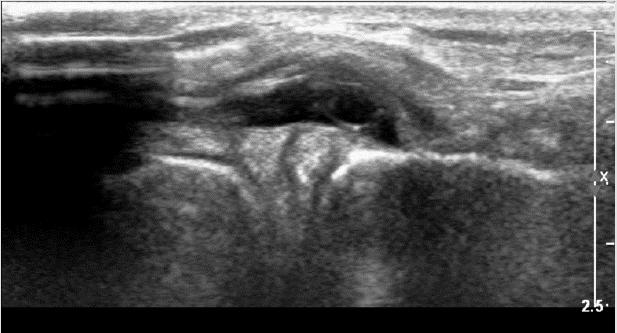

Figure 9 & 10: Osteoarthritis presented in MRI and US - severe narrowing of the medial compartment, disappearance of the medial meniscus, cartilage erosion, and mild subchondral oedema from both sides the medial compartment.